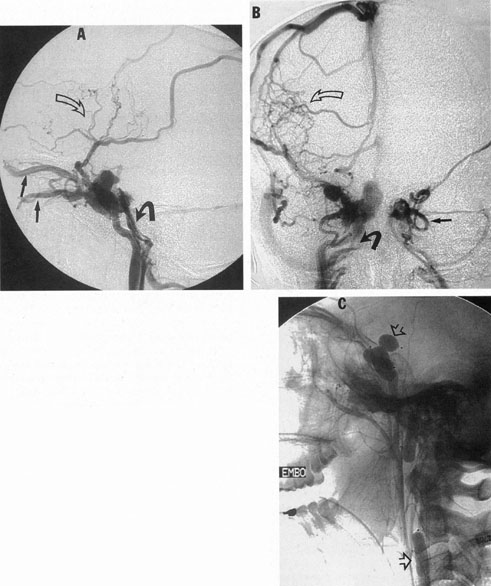

The therapy for AVMs has been reviewed elsewhere.91–93 The preferred treatment remains complete surgical excision of the malformation. However, significant advances in endovascular and radiosurgical techniques have resulted in a marked increase in the use of multimodal, staged approaches to AVM treatment. A variety of intravascular techniques use embolization91 with materials such as particles of polyvinyl alcohol (PVA), platinum coils, and injection of liquid N-butyl-cyanoacrylate (NBCA) adhesive (Fig. 11). Complications of intravascular embolotherapy include vessel perforation by the catheter, migration of embolic materials, and infarction and hemorrhage of normal brain.

Fig. 11. Embolization of middle cerebral vessels that supply occipital lobe arteriovenous malformation (AVM). The patient had a subarachnoid and intraparenchymal hemorrhage that produced a left homonymous field defect. A: Right carotid arteriogram demonstrates contribution via posterior communicating artery to a right occipital lobe AVM. B: Vertebral injection. The arrow points to the enlarged right posterior cerebral artery that is a major feeder of the AVM. C: Right carotid arteriogram during glue embolization procedure. The arrow points to a catheter as it traverses the segment seen in (B). The catheter was advanced via the internal carotid artery but is positioned far posteriorly. D: Upper branches to the AVM now are occluded, with residual low-flow vascularization via the middle cerebral artery. E: Skull film showing radiopaque glue within the AVM and blood vessels previously supplying it. The patient had a persistent visual field defect but greatly reduced headache and no persistence of subjective bruit. (Courtesy of Dr. Joseph Horton.)

Mechanisms of delivery of radiation therapy to AVMs include those of the linear accelerator (LINAC), gamma knife, and heavy charged particle beam (proton and helium ion Bragg-peak radiosurgery). Stereotactic radiosurgery is most commonly administered by gamma knife for a variety of intracranial disorders to include tumors and vascular malformations.94 Pollock et al61 believe that stereotactic radiosurgery is 80% effective for AVMs less than 3 cm in average diameter, within a latency period of 2 to 3 years, but the patient is at risk during the interval until obliteration of the lesion.